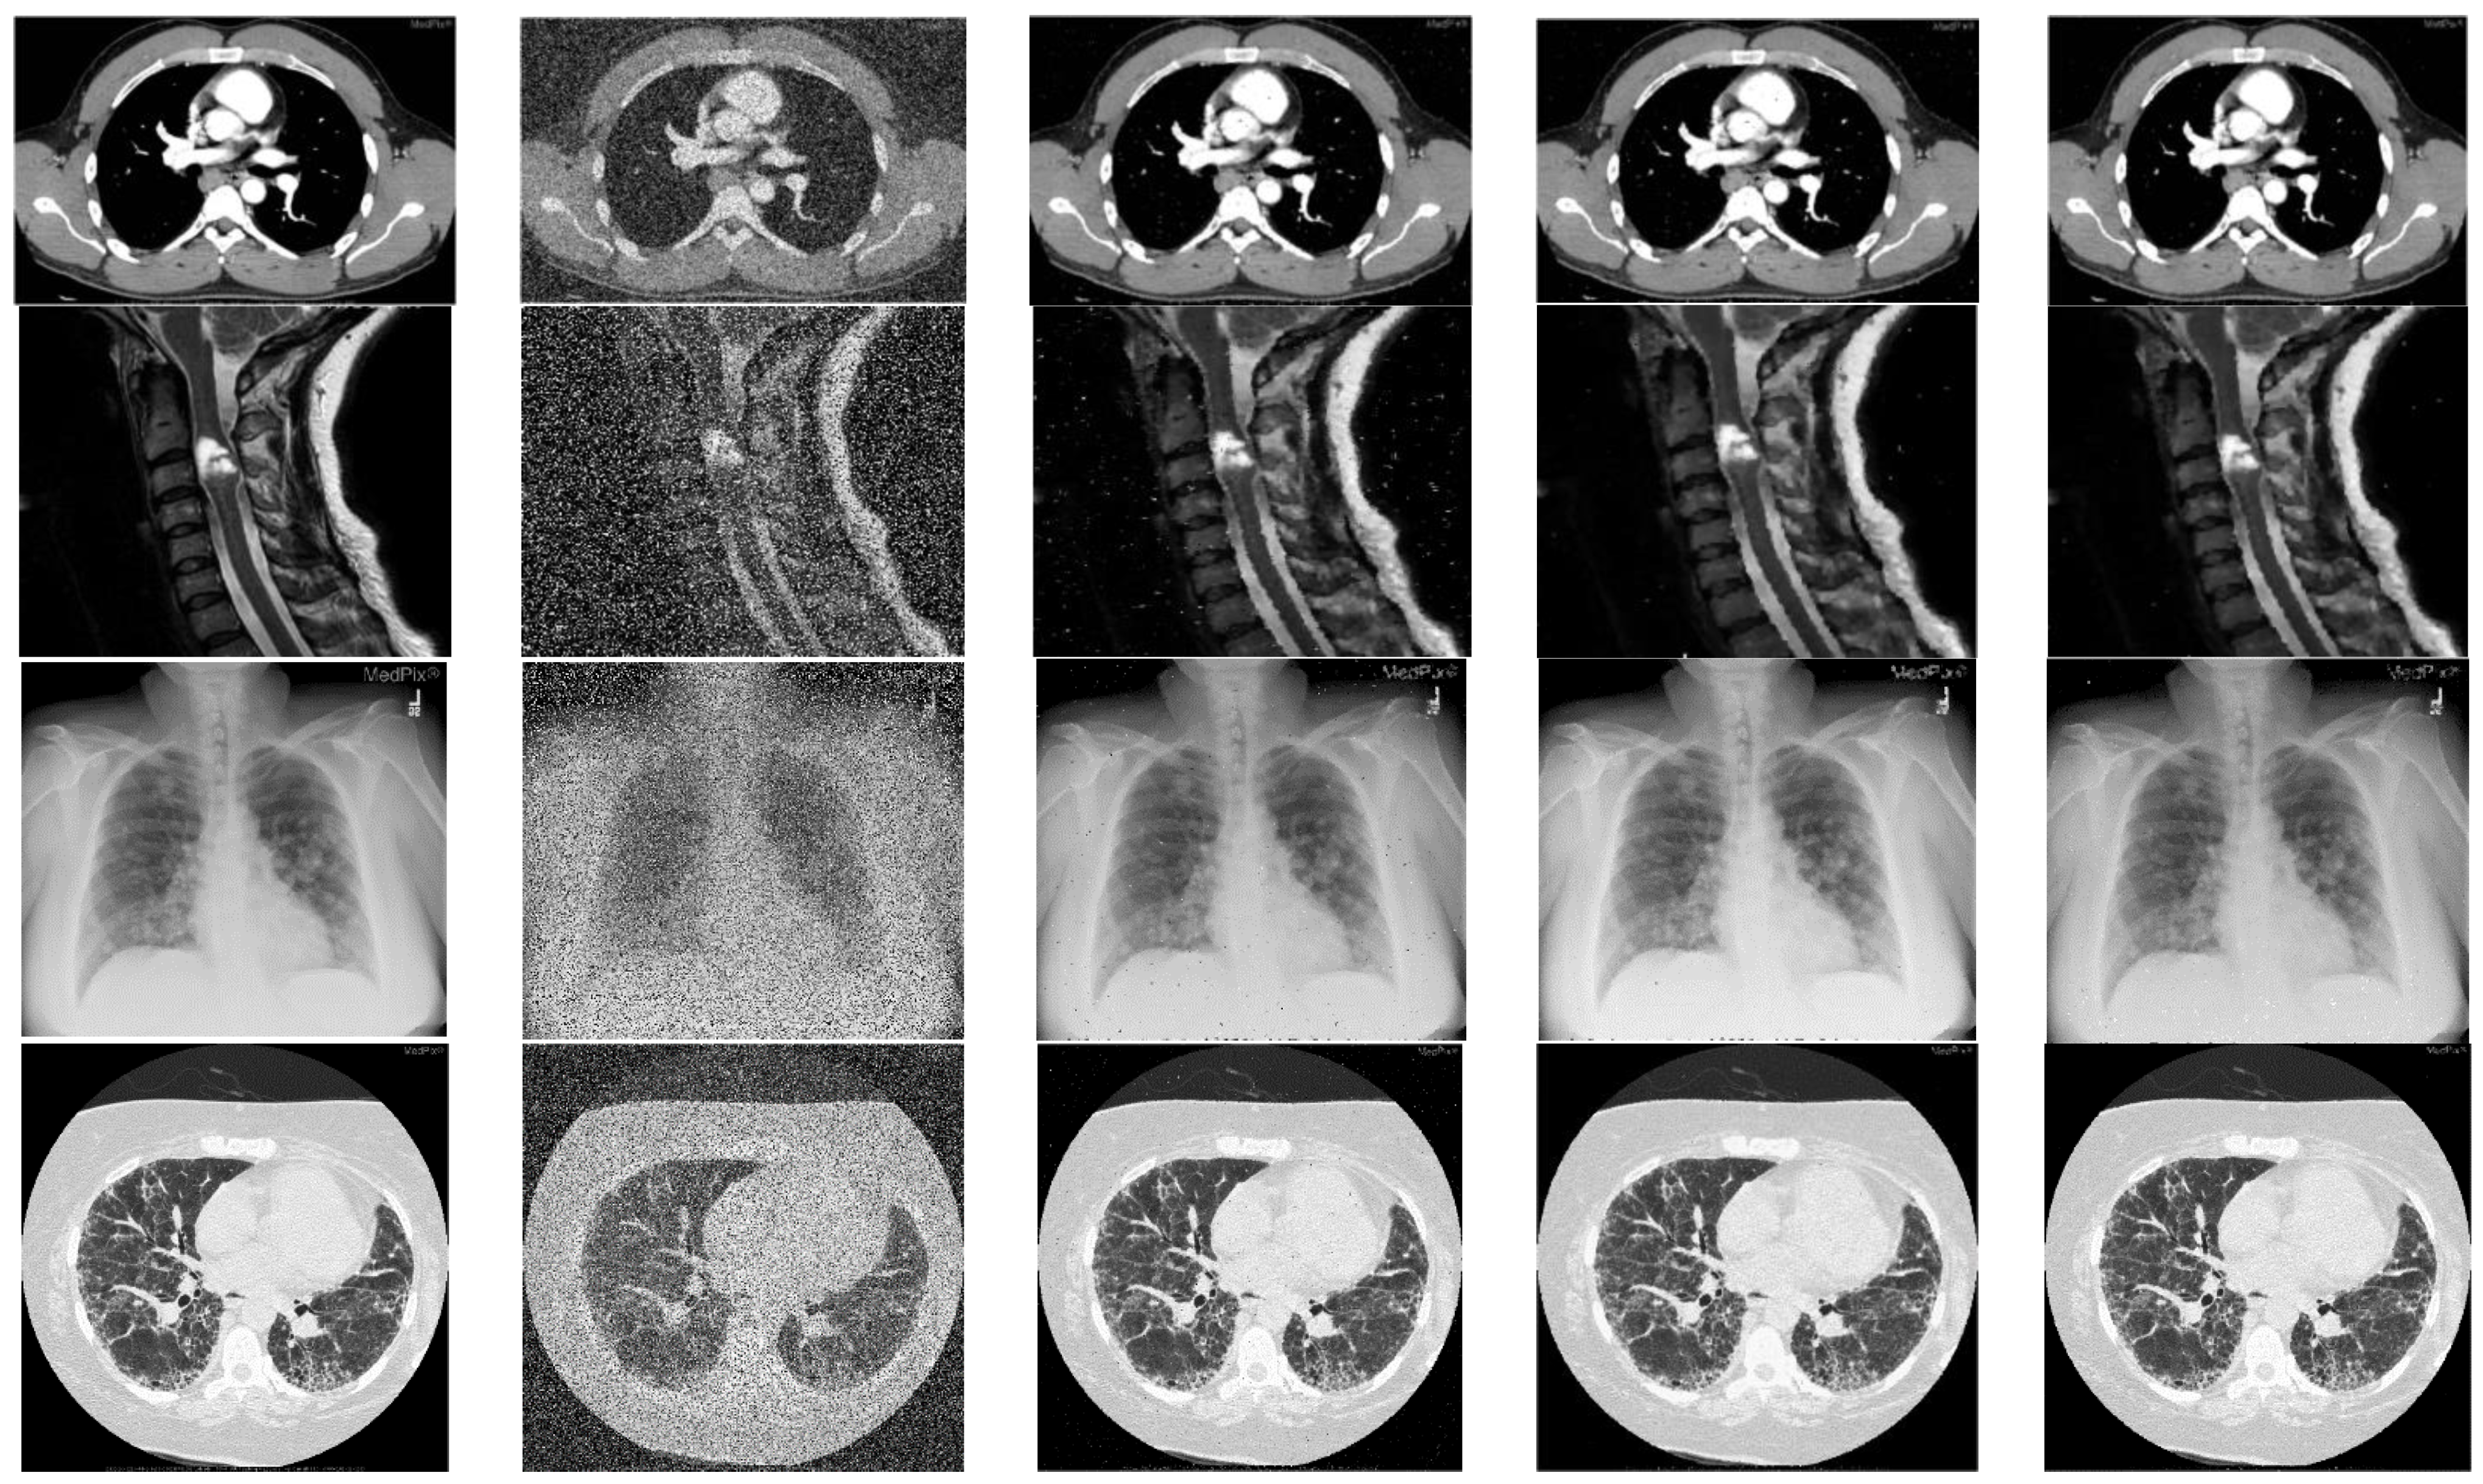

A subjective comparison is performed on a small sample of standard images as shown in Figure 6 as well as randomly selected medical images of MedPix dataset and the restoration results are shown in Figure 8, Figure 9 and Figure 10. In Figure 8, the restored images of NWM [29], SRM [40] and AEPWM [41] have some traces of noise clearly visible on the restored images whereas AFIDM [42], QSAF, TSA and the proposed filter de-noised the noisy image well. It is clear from the visual results that the proposed filter has preserved the edges and detailed regions of the Lena image very well as compared TSA, QSAF and other competing filters. The performance of the proposed filter is tested on detailed images, i.e., Baboon and Barbara, of size 512 × 512 at high noise densities, 50% and 60% RVIN, and the results are tabulated in Figure 9. It can be seen from the restored results that the proposed filter has effectively preserved the edges and fine details in both the images. Similarly, when the proposed technique is further tested on medical images of MedPix dataset as shown in Figure 10, it is clear from subjective results that the proposed filter outperforms QSAF and AFIDM filters. Figure 11 shows EPI values of different de-noising methods for Lena image at 30% noise ratio. It is evident from quantitative as well as subjective comparisons that the proposed filter gives best results and outperforms many existing filters against different noise densities ranging from low to high.

Figure 10.

Shows image restoration results on medical image dataset. 1st column are the original images from MedPix database, 2nd column are the noisy images with 40% RVIN, third column shows de-noised results using AFIDM filter, fourth column shows de-noised results using QSAF and fifth column shows restoration results of proposed filter.